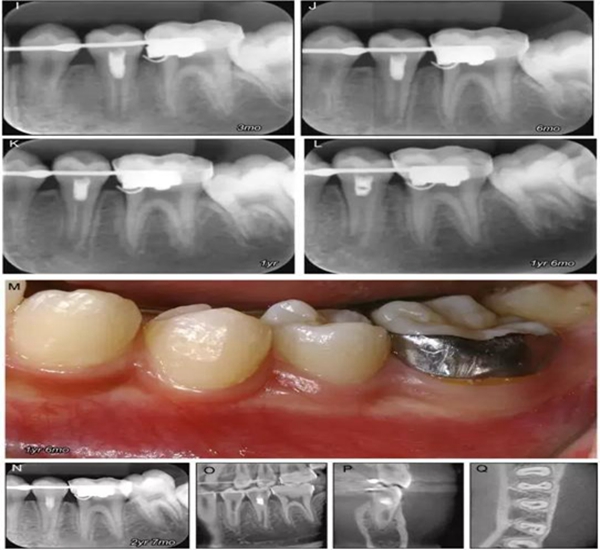

原則上年輕恒牙的牙髓治療應(yīng)盡可能以保存活髓的方式以便不影響牙根繼續(xù)發(fā)育。本文3個(gè)病例均描述了根尖尚未發(fā)育完成的下頜前磨牙被確診為牙髓壞死伴有大面積根尖病損,治療過(guò)程中在根管內(nèi)發(fā)現(xiàn)了部分活髓,而采用活髓切斷后都取得了很好的療效。